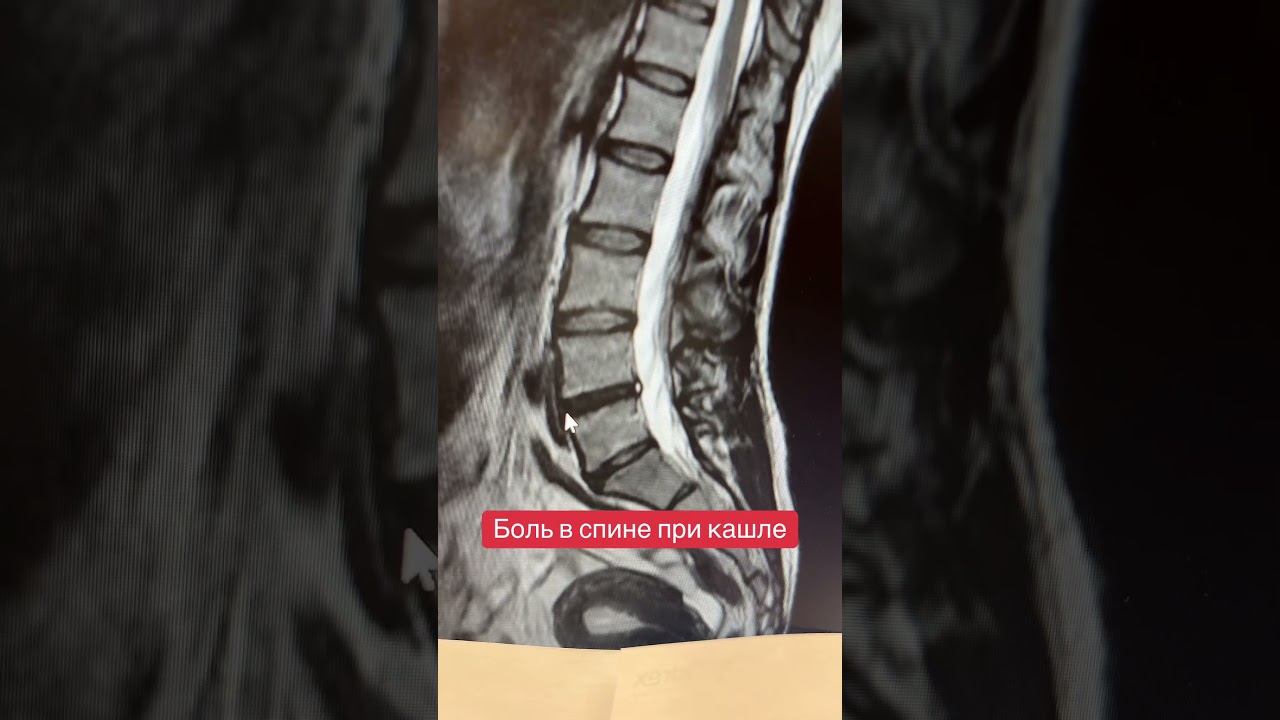

Врачи отмечают, что боль в спине при кашле может быть связана с различными причинами. Часто это связано с напряжением мышц, возникающим в результате интенсивного кашля, особенно если он длительный или мучительный. В таких случаях спазмы мышц спины могут вызывать дискомфорт. Однако, специалисты предупреждают, что подобные симптомы могут также указывать на более серьезные проблемы, такие как заболевания легких, межреберная невралгия или даже патологии позвоночника. Поэтому важно не игнорировать такие проявления и обратиться к врачу для диагностики. Правильное лечение и рекомендации помогут избежать осложнений и улучшить качество жизни пациента.

Пациент направляется на анализы (мочи, крови, мокроты и др.) и инструментальные обследования, такие как УЗИ, ЭКГ, МРТ и рентген. На основе собранных данных можно точно определить, что вызывает боли в спине при кашле — от простого перенапряжения мышц до серьезных проблем, например, остеохондроза.

Если вы хотите узнать больше о процедуре МРТ позвоночника и ее результатах, ознакомьтесь с соответствующей статьей на нашем сайте.